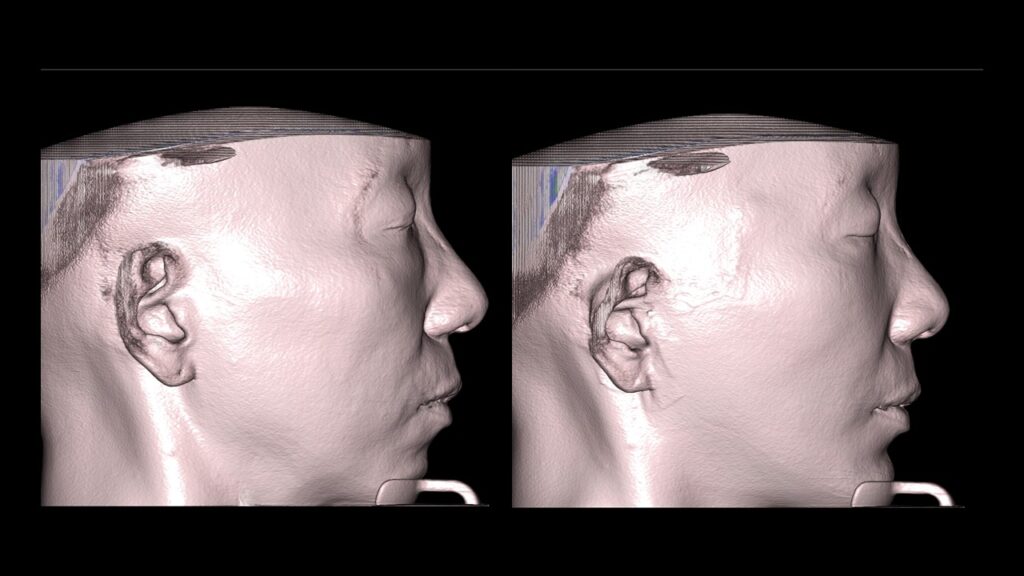

4. Case Studies (3DCT & Medical Photos)

-

Case 2: (Zygoma + Chin Advancement + Face Lift + Brow Lift) Dramatic improvement in the side profile and double chin within just 1 month.